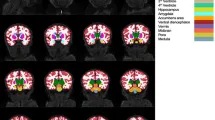

Из 66 детей с ДТВ, 61 нейровизуализационная последовательность была включена в окончательный нейровизуализационный анализ, и 5 детей были исключены due to артефактов движения. Не было значимых различий в основных демографических и клинических переменных (возраст, пол, раса, образование, количество клеток CD4+, вирусная нагрузка, АРТ) между 61 включенным ребенком и 15 детьми без данных сканирования.

Корреляция показателей ДТВ и мотивации

Были проведены двумерные анализы балла CMS и показателей ДТВ в априорных регионах. Статистически значимые корреляции между CMS и fractional anisotropy (FA — фракционная анизотропия, мера направленной зависимости диффузии воды, отражающая микроструктурную целостность белого вещества), mean diffusivity (MD — средняя диффузия, средняя величина диффузии воды во всех направлениях) и radial diffusivity (RD — радиальная диффузия, диффузия воды перпендикулярно основному направлению волокон) показаны в соответствующей таблице. Отрицательные корреляции наблюдались между CMS и FA в передней ножке внутренней капсулы с обеих сторон и superior corona radiata (справа), и положительные корреляции с MD в поясной извилине (справа) и RD в поясной извилине (с обеих сторон).

Используя ДТВ, мы identified взаимосвязь между баллом мотивации и микроструктурой белого вещества, similar to исследованиям апатии и ВИЧ у взрослых. В частности, показатели ДТВ в передней ножке внутренней капсулы, superior corona radiata и поясной извилине коррелировали с баллом CMS, что suggests целостность белого вещества в этих регионах связана с мотивацией.

Анатомическая значимость фронтостриатальных путей

Передняя ножка внутренней капсулы — это white matter подсоковая структура, расположенная между хвостатым ядром (медиально) и чечевицеобразным ядром (латерально). Она predominantly содержит таламические и стволовые волокна, соединяющие таламус с префронтальной корой (таламокортикальные и кортикоталамические), и лобную долю с ядрами моста (frontopontine), а также поперечные волокна, соединяющие хвостатое ядро и скорлупу. Известно, что передняя ножка внутренней капсулы важна во фронтостриатальных путях, которые часто поражаются ВИЧ.